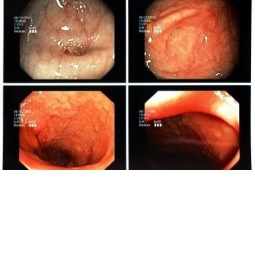

W ostatnim wydaniu Colorectal Disease ukazała się meta-analiza podsumowująca wiedzę na temat przydatności insuflacji przewodu pokarmowego dwutlenkiem węgla w czasie kolonoskopii.

W analizie uwzględniono randomizowane kontrolowane badania, w których porównywano efektywność i akceptowalność kolonoskopii wykonywanej metodą klasyczną z insuflacją powietrza z kolonoskopią, podczas której stosuje się insuflację jelita dwutlenkiem węgla.

Zidentyfikowano 21 badań, spełniających zdefiniowane kryteria, które obejmowały populację 3607 chorych. Wykazano, że insuflacja dwutlenkiem węgla wiązała się z istotnie mniej nasilonym bólem w trakcie badania, a także po kolonoskopii – 6 godzin, jak i 24 godzin po wykonaniu badania endoskopowego jelita grubego. Wykazano także, że insuflacja dwutlenkiem węgla wiązała się z krótszym czasem niezbędnym do osiągnięcia kątnicy, aczkolwiek nie było istotnych różnic w odsetku wykonania pełnych badań kolonoskopowych.

Jak więc podkreślają autorzy meta-analizy, dotychczas zgromadzone dane sugerują, że insuflacja dwutlenkiem węgla ma szereg przewag nad insuflacją powietrzem, podczas badania kolonoskopowego.